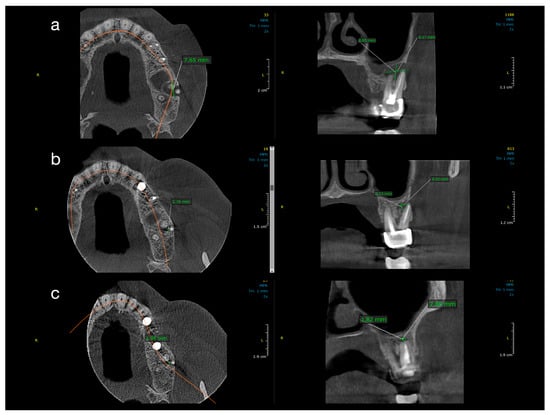

Figure 2. Sequential CBCT images of a case from Group 1 (conventional treatment). Axial, sagittal, and coronal CBCT slices showing lesion reduction in a patient treated with conventional root canal therapy and calcium hydroxide. (a) Baseline: well-defined radiolucency measuring 7.65 mm mesiodistally, 6.55 mm buccolingually, and 9.17 mm vertically. (b) One-year follow-up: partial healing with reduction to 2.78 mm (MD), 3.13 mm (BL), and 4.3 mm (V). (c) Two-year follow-up: near-complete resolution (1.96 mm MD, 1.82 mm BL, 2.69 mm V).

Figure 3. Sequential CBCT images of a case from Group 2 (decompression). Radiographic healing in a patient treated with root canal therapy and adjunctive decompression. (a) Baseline: critical-size lesion with dimensions of 12.11 mm (MD), 10.37 mm (BL), and 10.38 mm (V). (b) At 1 year: significant size reduction to 4.45 mm (MD), 3.67 mm (BL), and 3.84 mm (V). (c) At 2 years: residual lesion measuring ~3.67 mm in height and ~3.5 mm in width.

Figure 2 and Figure 3 illustrate representative cases from each group, highlighting the volumetric healing over time. In a Group 1 case (conventional treatment only), the initial lesion (~8–10 mm in diameter in each dimension) showed substantial shrinkage by the 1-year follow-up and almost complete radiological resolution by 2 years. By contrast, a Group 2 case (with decompression), which began with a larger cystic lesion (over 12 mm in its greatest dimension), demonstrated a dramatic reduction in lesion size after 12 months of decompression and continued healing at 24 months, leaving only a small residual radiolucency. These examples underscore the progressive radiographic healing observed in both treatment protocols.

All ten treated teeth remained asymptomatic throughout the follow-up, and sequential CBCT evaluations confirmed continuous lesion regression in every case. Table 1 and Table 2 detail the lesion size measurements (in mm) for each patient at baseline, 1 year, and 2 years in Group 1 and Group 2, respectively. Many lesions exhibited complete or near-complete radiological healing by the end of the observation period (recorded as 0.00 mm lesion diameter in at least one dimension for several cases in both groups). At baseline, Group 2 lesions were notably larger than those in Group 1. The mean initial lesion diameter in Group 2 was 13.7 mm (±3.34), compared to 7.3 mm (±1.74) in Group 1 (Table 3). This difference was statistically significant (p < 0.001), confirming that Group 2 started with more extensive periapical lesions. It is noteworthy that the baseline lesion size data in both groups showed no significant departures from normal distribution (see Table 4 for normality test results), which validated the use of parametric statistical comparisons.

By the 12-month follow-up, the lesion dimensions had decreased markedly in both groups (Table 3). In Group 1 (standard endodontic therapy), the mean lesion diameter reduced from 7.3 mm at baseline to 2.93 mm (±0.75) at one year. In Group 2 (endodontic therapy + decompression), the mean lesion diameter decreased from 13.7 mm to 5.21 mm (±4.75) at one year. Although the lesions in Group 2 remained larger in absolute terms after 12 months, the difference between the two groups was no longer statistically significant (p = 0.087). Figure 4 presents violin plots of the lesion size distributions at baseline and one year, illustrating the substantial shift toward smaller lesion diameters in both cohorts. The spread of the violin plot for Group 2 at one year was broader, reflecting greater variability in healing outcomes among those larger initial lesions. By the 24-month follow-up, both groups showed further improvement. Group 1 lesions had a mean diameter of 1.12 mm (±0.98), and Group 2 lesions averaged 2.41 mm (±5.15). This slight residual difference was not statistically significant (p = 0.356). Radiographically, most lesions in both groups had resolved or nearly resolved by two years, with only very small radiolucencies, if any, remaining. It was observed that Group 2 continued to exhibit a higher variability in lesion size outcomes at 24 months (as evidenced by a larger standard deviation and wider confidence interval in Table 3). Importantly, within each group, the reduction in lesion size from baseline was highly significant. Both Group 1 and Group 2 demonstrated statistically significant lesion shrinkage at the 1-year and 2-year evaluations compared to baseline (intragroup comparisons, p < 0.001 for all). This confirms that both treatment approaches achieved effective and progressive lesion resolution over time in their respective groups.